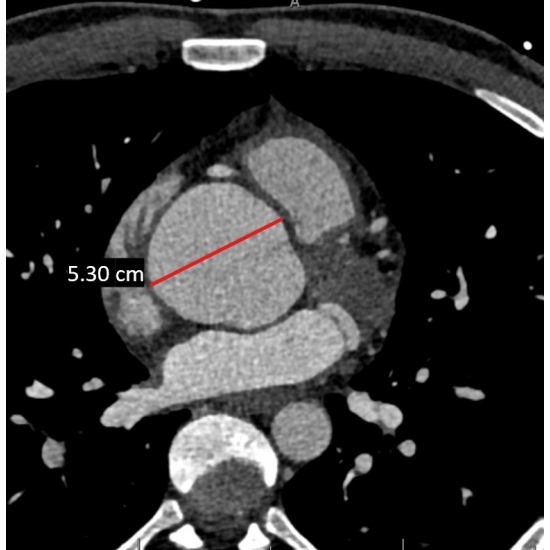

Screening electrocardiogram revealed atrial fibrillation with a ventricular rate of 94 beats per minute Case Photo #1 , and a three-day Holter monitor resulted in a 100 percent atrial fibrillation burden with an average heart rate of 110 beats per minute Case Photo #2 . A transthoracic echocardiogram showed severe aortic sinus and ascending aorta dilation to a maximum diameter of 5.10 centimeters (at his age, normal is considered 2.5 centimeters to 3.5 centimeters). It also revealed a mildly dilated left ventricle with normal wall thickness, systolic function, and diastolic function. It showed mild right ventricle dilation with normal systolic function. Mild aortic, mitral, tricuspid, and pulmonic regurgitation was present. The inferior vena cava was mildly dilated. Computerized tomography angiography confirmed the presence of a dilated aortic root with a maximum diameter of 5.30 centimeters at the sinus of Valsalva Case Photo #3 . On review of imaging records from his prior school, he received a screening transthoracic echocardiogram as a part of his pre-participation evaluation, which revealed the initial aortic root dilation. Subsequent workup at his previous school with a CT angiogram revealed a maximum diameter of the aortic root of 5.10 centimeters one year ago. Cardiac magnetic resonance imaging with and without intravenous contrast reiterated all findings as noted above and showed that the aortic size was normal above the level of the mid-ascending aorta Case Photo #4 . Computerized tomography coronary angiography was done about two months after the initial imaging listed above, which revealed no coronary artery atherosclerosis and revealed a maximum aortic root dilation of 5.60 centimeters Case Photo #5 . Based on these results, he had an aortic root z-score of 7.90 (normal variance is negative 2 to positive 2). (1-2)